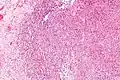

Micrograph of an epithelioid sarcoma. H&E stain.

Histologically, epithelioid sarcoma forms nodules with central necrosis surrounded by bland, polygonal cells with eosinophilic cytoplasm and peripheral spindling.[3] Epithelioid sarcomas typically express vimentin, cytokeratins, epithelial membrane antigen, and CD34, whereas they are usually negative for S100, desmin, and FLI1 (FLI-1).[3] They characteristically lack the protein INI1 (see below). Epithelioid sarcomas typically stain positive for CA125.[4]